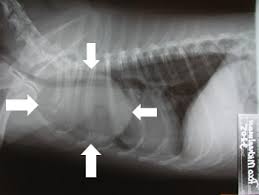

The most important cause to exclude is a form of lung cancer, including rare forms such as primary pulmonary lymphoma, carcinoid tumor and a solitary metastasis to the lung (common unrecognised primary tumor sites are melanomas, sarcomas or testicular cancer). Benign tumors in the lung include hamartomas and chondromas. The most common benign coin lesion is a granuloma (inflammatory nodule), for example due to tuberculosis or a fungal infection. Other infectious causes include a pulmonary abscess, pneumonia (including Pneumocystis carinii pneumonia) or rarely nocardial infection or worm infection (such as dirofilariasis or dog heartworm infestation). Lung nodules can also occur in immune disorders, such asrheumatoid arthritis or Wegener's granulomatosis, or organizing pneumonia.

An SPN can be found to be an arteriovenous malformation, a hematoma or an infarction zone. It may also be caused by bronchial atresia, sequestration, an inhaled foreign body or pleural plaque. Several features help to distinguish benign conditions from possible lung cancer. The first parameter is the size of the lesion: the smaller, the less risk for malignant cancer. Benign causes tend to have a well defined border, whereas lobulated lesions or those with an irregular margin extending into the neighbouring tissue tend to be malignant.  If there is a central cavity, then a thin wall points to a benign cause whereas a thick wall is associated with malignancy (especially 4mm or less versus 16mm or more). In lung cancer, cavitation can represent central tumor necrosis (tissue death) or secondary abscessformation. If the walls of an airway are visible (air onchogram), bronchioloalveolar carcinomais a possibility. An SPN often contains calcifications. Certain patterns of calcification are reassuring, such as the popcorn-like appearance of hamartoma. An SPN with a density below 15 Hounsfield units on computed tomography tends to be benign, whereas malignant tumors often measure more than 20 Hounsfield units. Fatty tissue inside hamartomas will have a strongly negative value on the Hounsfield scale. The growth velocity of a lesion is also informative: very fast or very slow growing tumors are rarely malignant, in contrary to inflammatory or congenital conditions. It is therefore important to retrieve previous imaging studies to see if a lesion was presented and how fast its volume is increasing. This is more difficult for nodules smaller than 1 centimeter. Moreover, the predictive value of stable lesion over a period of 2 years has been found to be rather low and unreliable. The work-up in patients with a solitary pulmonary nodule is based on an initial risk assessment. If the risk of malignancy is thought to be low, follow-up imaging (usually serial CT scans) can be planned at a later time. The frequency of further scans can be determined by the patient's risk for cancer and the size of the nodule. If the initial impression is that there is a high likelihood of cancer, then a surgical intervention is appropriate (provided that the patient is fit for surgery). If there is an intermediate risk of malignancy, further imaging with positron emission tomography (PET scan) is appropriate (if available). Around 95% of patients with a malignant nodule will have an abnormal PET scan, while around 78% of patients with a benign nodule will look normal on PET (this is the test sensitivity and specificity). Thus, an abnormal PET scan will reliably pick up cancer, but several other types of nodules (inflammatory or infectious, for example) will also show up on a PET scan. If the nodule has a diameter below 1 centimeter, PET scans are often avoided because there is an increased risk of falsely normal results. Cancerous lesions usually have a high metabolism on PET, as demonstrated by their high uptake of FDG (a radioactive sugar). If the lesion is found on further imaging to be suspicious, it should be surgically excised (via thoracotomy or video-assisted thoracic surgery) to confirm the diagnosis by microscopical examination.